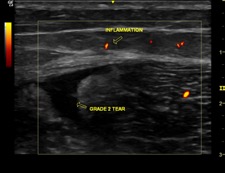

If there is a lot of bruising within 72 hours then it is advisable to get a scan on the injury in order to accurately diagnose the grade of tear and predict the likely time out of sport. Ultrasound scans are excellent for detecting muscle tears and can help predict return to play times. Below is the image of a grade 2 hamstring tear as was seen in this case study.

In the case example shown above I expect this elite sprinter to return to sport in 6-8 weeks. We will be closely monitoring the muscle recovery with ultrasound imaging to determine when it is safe to return to sport.

- Not getting the tear properly diagnosed. Muscle injuries can be effectively diagnosed and monitored with ultrasound scans and are much more cost effective than MRI scans. Ultrasound scans can also be used to determine when an athlete can safely return to play.